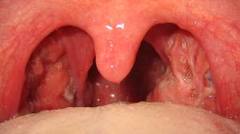

Cat Costa O Operatie De Amigdale